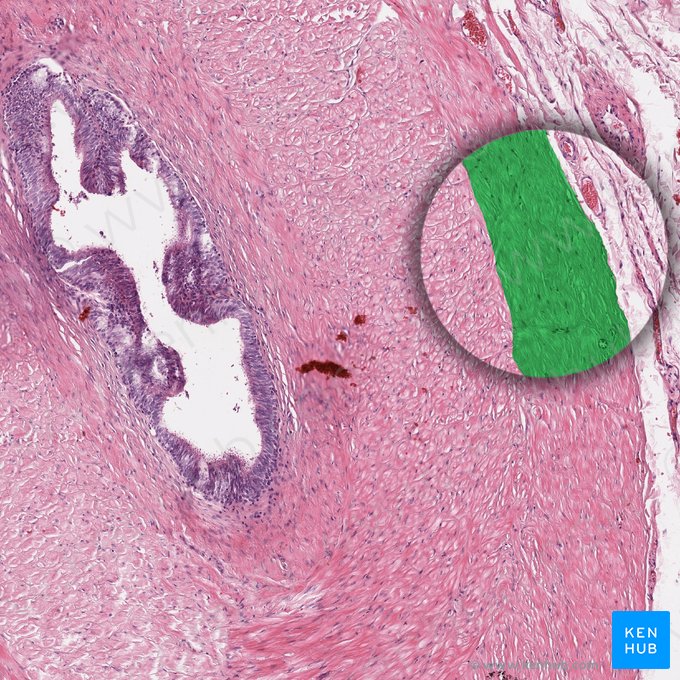

Der Ductus deferens hat eine dicke, dreischichtige Muskelwand, weshalb er im Samenstrang gut zu tasten ist. Das Lumen ist sternförmig und aufgrund der mehrschichtigen glatten Muskulatur sehr eng. Das Epithel besteht aus einem zwei- oder mehrreihigem Zylinderepithel mit Stereozilien, unter dem eine dünne Lamina propria liegt. Außen schließt sich eine Tunica adventitia aus lockerem kollagenem Bindegewebe an.